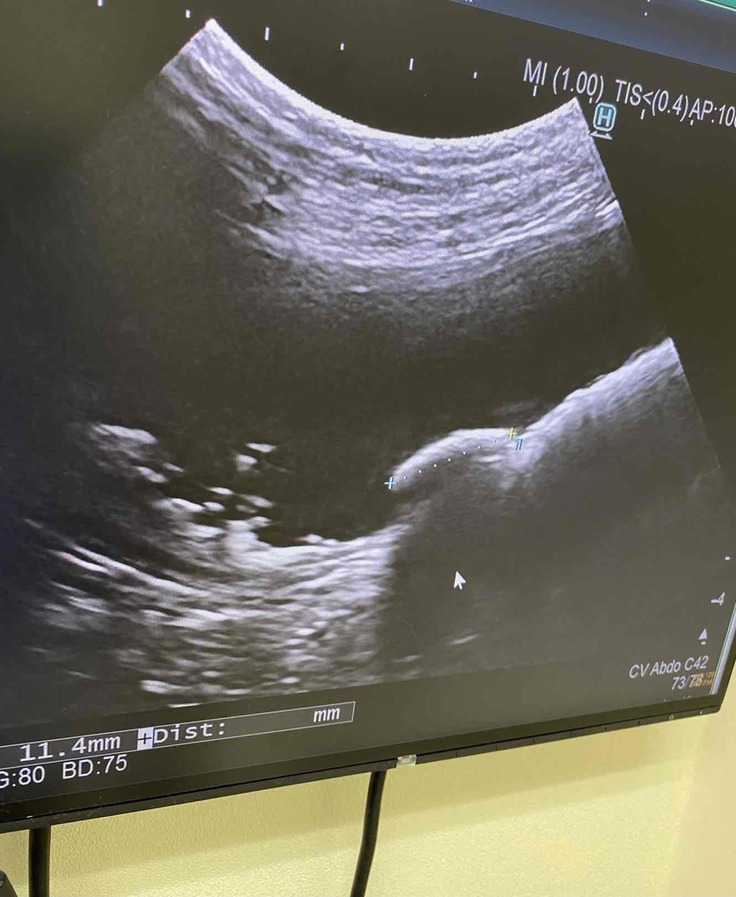

セカンドオピニオンにて超音波検査と血液検査。

また、超音波検査で膀胱内の結石も多数確認でき、一番大きいもので1.1cmの石を確認。

真ん中右寄りにあるのが一番大きな結石

それ以外にも小さい白い影で石が沢山…